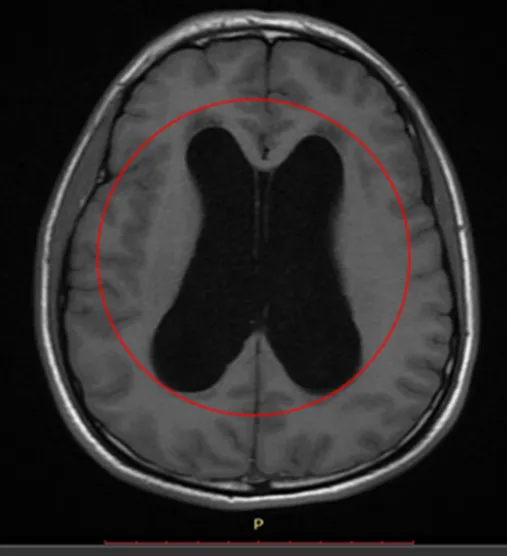

Resonancia Magnética Cerebral Simple

Hallazgo en RNM Cerebral

A nivel de brazo anterior de capsula interna derecha se observa pequeña área con cambios de intensidad de la señal de comportamiento magnético isointenso en T1 con respecto a la sustancia gris, e hiperintenso en T2 con restricción hídrica en difusión, mide 6.0 mm x 5.0 mm en sus mayores ejes sin repercusión sobre estructuras adyacentes.

Se observa dilatación simétrica en ventrículos laterales así como de tercer y cuarto ventrículo, este último provocando desplazamiento de mesencéfalo y parénquima cerebeloso en sentido anterior y posterior respectivamente, asociada a hiperintensidad moderada de la sustancia blanca periventricular en secuencia FLAIR en relación con edema intersticial.